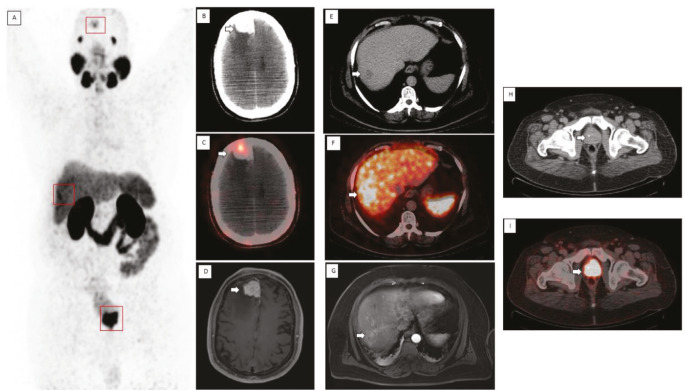

镓-68前列腺特异性膜抗原正电子发射断层扫描联合计算机断层扫描(68Ga PSMA PET-CT)是一种受体特异性成像,越来越多地用于前列腺癌(PCa)的分期和再分期。PSMA是在正常前列腺组织细胞质中表达的II型跨膜糖蛋白,在前列腺癌中超表达100-1000倍。它也在移行细胞癌、肾细胞癌、肝细胞癌、甲状腺癌和脑癌等非前列腺实体瘤的肿瘤相关新血管内皮中表达。我们在此提出一个病例,PSMA PET扫描显示三个肿瘤证实在随访成像。

Galium-68 prostate-specific membrane antigen positron emission tomography combined with computed tomography (68Ga PSMA PET-CT) is receptor specific imaging, which has increasingly been used in the staging and restaging of prostate carcinoma (PCa). PSMA is type II transmembrane glycoprotein expressed in cytosol of normal prostatic tissue with 100-1000-fold over expression in PCa. It is also expressed in the endothelium of tumor-associated neo vasculature of non-prostatic solid tumor such as transitional cell and renal cell carcinoma, hepatocellular, thyroid, and brain cancers. We hereby present a case where PSMA PET scan showed three tumors proved on follow up imaging.